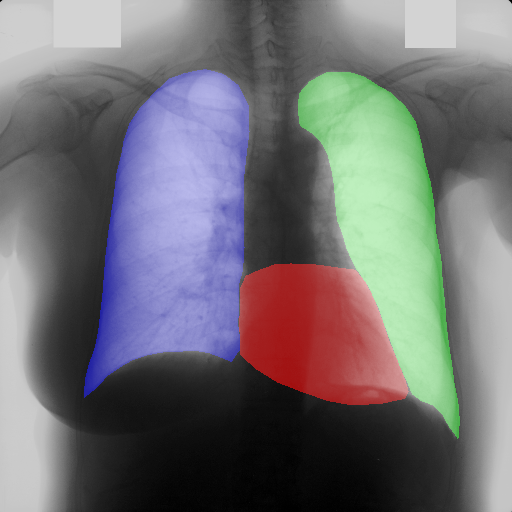

In this section, some examples of images and corresponding segmentations, generated with the approaches described in Section 3, are qualitatively examined. We also report some comments from three physicians on the generated segmentations, to provide a medical assessment of the quality of our method.

Figure 5 and Figure 6 display some examples — randomly chosen from all the generated images — of the label–maps and the corresponding chest X–ray images generated with the three methods described in Section 3, using the FULL_DATASET and the TINY_DATASET, respectively. We can observe that, with the single and two–stage methods, the images tend to be more similar to those belonging to the training set. For example, in most of the generated images there are white rectangles, which resemble those present in the training images, used to cover the names of both the patient and the hospital. Instead, the three–stage method does not produce such artifacts, suggesting that it is less prone to overfitting.